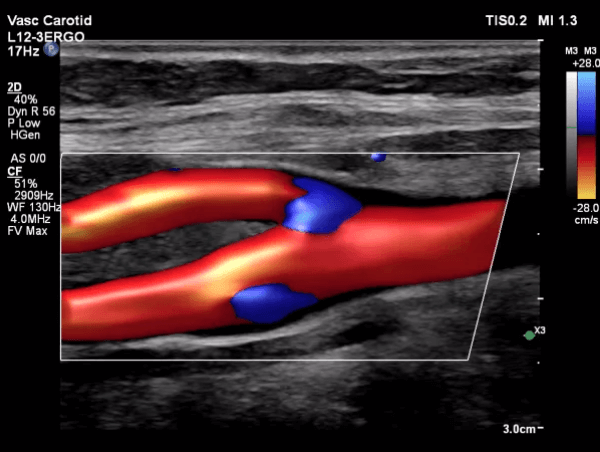

Carotid Artery Ultrasound

This test examines the arteries in the neck, allowing visualization of plaque without radiation exposure. This is the source of most strokes, and can be detected years before symptoms occur. Dr. Ghalichi performs this operator-dependent scan himself, using Philips Healthcare software to measure the carotid intima-media thickness (CIMT) with high precision.

Carotid Ultrasound